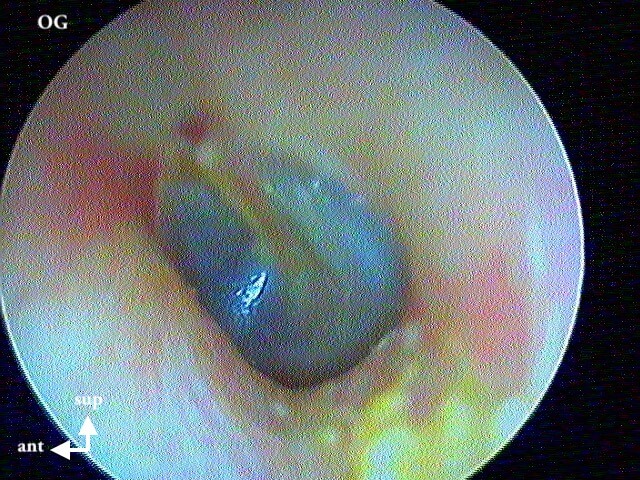

Ici une otite séromuqueuse gauche perforée cicatrisée à 1 mois (cicatrice inférieure)

L' aspect est difficile à voir chez les enfants (j'utilise un endoscope 0° 2,7mm de diamètre d'où la petite image): c'est finalement une otite séromuqueuse gauche perforée et non otite moyenne aiguë.